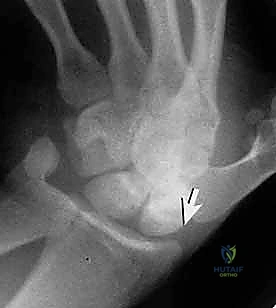

- الأشعة السينية الخاصة (Scaphoid Views): الأشعة السينية العادية للرسغ قد لا تظهر الكسر. يطلب الدكتور هطيف وضعيات تصوير محددة (أربع وضعيات مختلفة مع انحراف اليد) لتوضيح عظم الزورقي بشكل كامل. مع ذلك، ما يقارب 15% إلى 20% من كسور الزورقي تكون "خفية" (Occult Fractures) ولا تظهر في الأشعة السينية في الأسبوع الأول.

- الأشعة المقطعية (CT Scan): يفضل الأستاذ الدكتور محمد هطيف استخدام الأشعة المقطعية ثلاثية الأبعاد (3D CT Scan) للتخطيط الجراحي. فهي توفر خريطة دقيقة جداً لحجم الكسر، زاوية الانحراف، وتساعد في تحديد مسار المسمار بدقة مليمترية قبل الدخول إلى غرفة العمليات.

تقنية "التثبيت عن طريق الجلد" (Percutaneous Fixation) هي إجراء جراحي طفيف التوغل (Minimally Invasive). بدلاً من فتح الرسغ، يقوم الجراح بإجراء ثقب صغير جداً في الجلد (لا يتجاوز 3-5 مليمترات). من خلال هذا الثقب، وباستخدام جهاز الأشعة السينية المباشر في غرفة العمليات (C-arm Fluoroscopy)، يتم إدخال سلك توجيهي دقيق، ثم يتم إدخال مسمار خاص يسمى "مسمار ضغط بدون رأس" (Headless Compression Screw) مثل مسمار هيربرت (Herbert Screw).